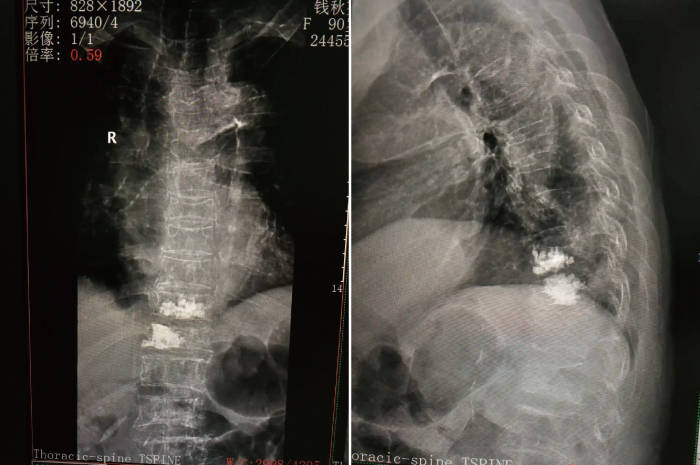

案例回顾 患者钱某 , 女 , 90岁 , 因胸背部及肋腹部疼痛1月 , 加重1周入院 。 在某医院以腹痛诊治 , 没有明显效果 , 为进一步治疗来杭州城东医院就诊 。

入院后 , 查胸腰椎X线示:T8-T12多发椎体楔形改变 , 椎体骨质脱钙明显;椎体MRI示:T10-T11胸椎压缩性骨折 , STIR信号增高 。

明确诊断:①胸10、胸11椎体压缩性骨折;②重度骨质疏松症 。

(术前x片)